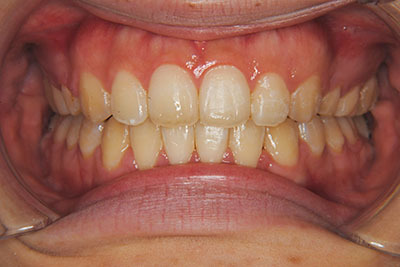

おとなの方でも矯正治療をあきらめないでください!

矯正歯科治療は子供の頃だけしかできない……

子供の頃に比べ大人になったら治療期間がすごく長い……

というようなイメージをお持ちではありませんか?

子供の頃に矯正治療を行う方が治療期間が短く済むというのは、確かですが、矯正治療は患者様の意識も重要です。

いくら歯が動き易くとも、本人がやる気でなければ効果は出ませんし、むし歯発生のリスクも高まります。おとなの方は顎の成長が終わっているため、治療の計画が立てやすいとも言えます。「もう大人だから…」とあきらめず、一度ご相談ください。